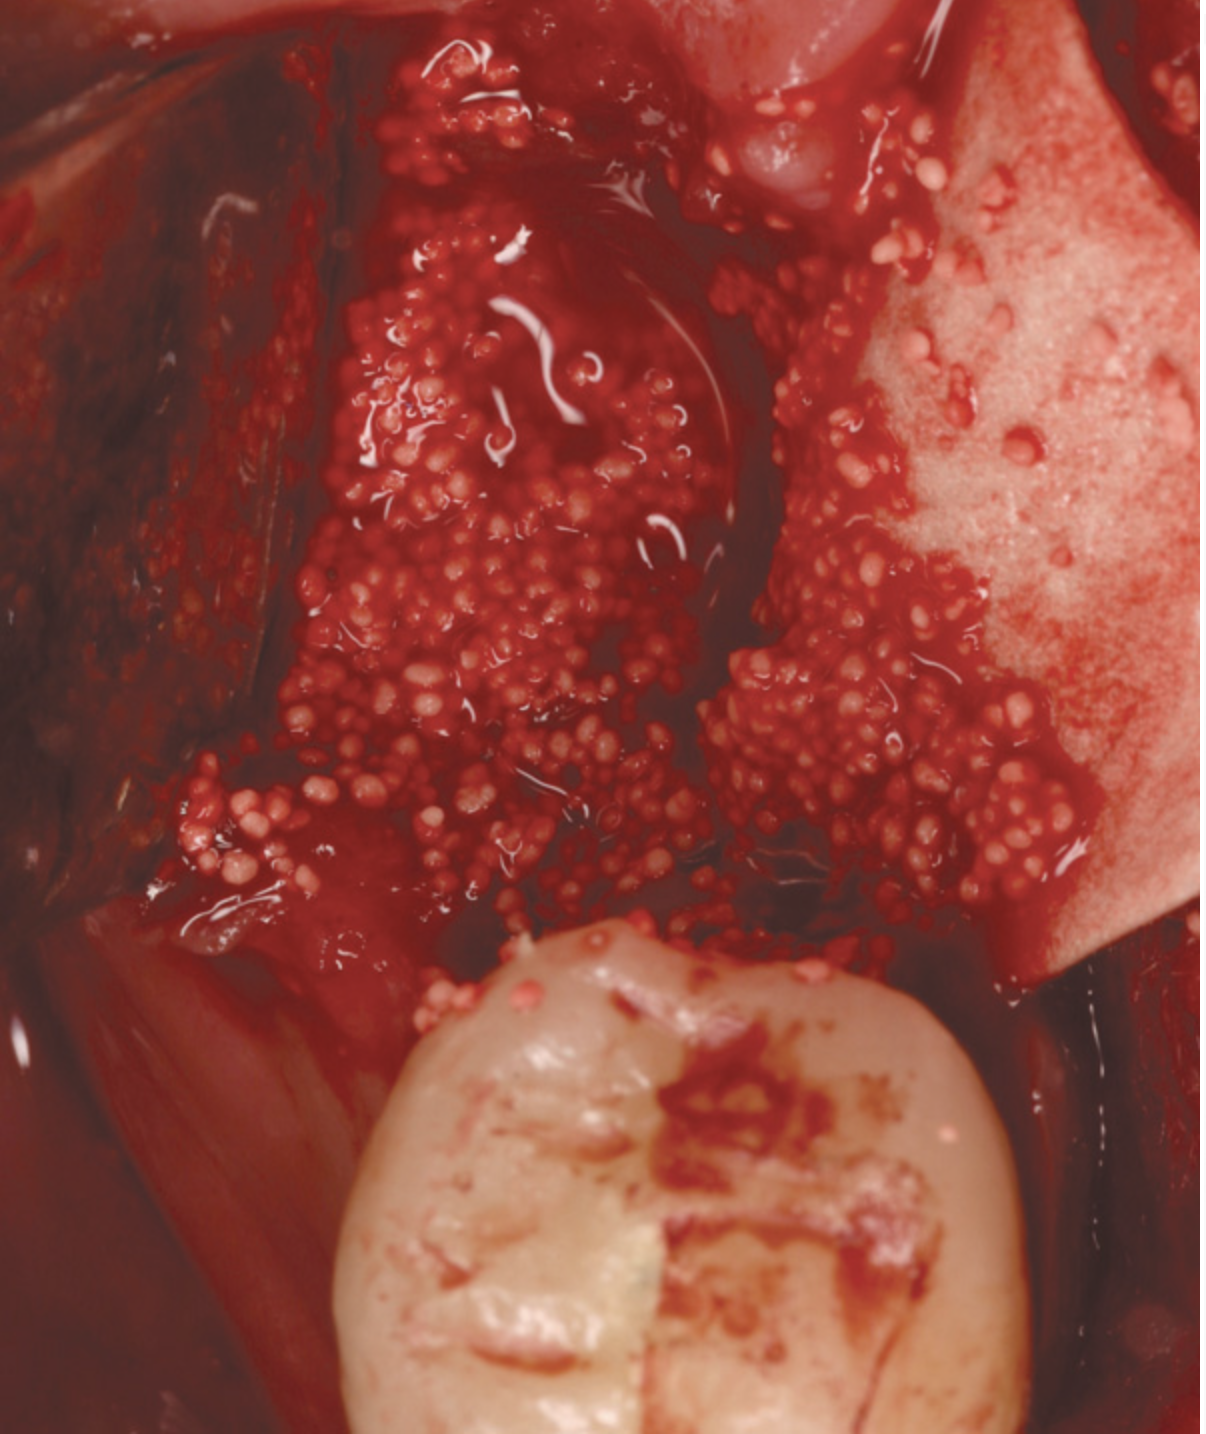

Other graft materials that have been used at the time of tooth extraction include synthetic materials. Calcium sulfate has been used in many configurations as a graft and/or enhancer (Figure 1). A 2004 study showed excellent volume preservation and that close to 60% vital bone formed when a hemihydrate form of calcium sulfate was used with no barrier.5 A novel bone replacement graft material described in a 2012 report is biphasic in nature, containing both hemi- and di-hydrate calcium sulfate. This material is self-setting in the presence of blood or saliva, is reinforced, and can be used with or without a barrier membrane.6 The report presented findings on its use in multiple types of defects, all demonstrating significant amounts of bone histologically. In addition, there was significant preservation or augmentation of the alveolar ridge width.

The patient shown in Figure 1 had presented after significant endodontic-related abscesses reduced the height of both buccal and lingual plates of bone. Covering the biphasic calcium sulfate (BPCS) graft with a dense polytetraflouroethylene (PTFE) barrier for 3 weeks enhanced healing in the site. Clinically, it is apparent that the ridge volume was maintained over 5 years and supported keratinized tissue (Figure 2). Most importantly, there was, on histologic evaluation, 58% vital bone, with no remnants of the bone replacement graft material (Figure 3).

Fig 1. A significant loss of bone necessitated covering the BPCS with a dense PTFE barrier.

Figure 1